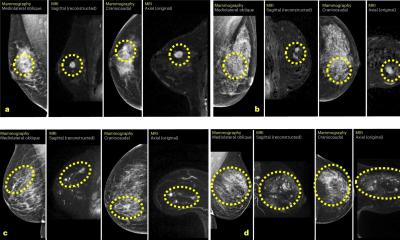

Breast cancer screening should become more personalised, not the “one size fits all” frequency of today

Ruud Pijnappel

In the United Kingdom, mammography breast cancer screening is offered to women ages 50 to 75 every three years. The Breast…